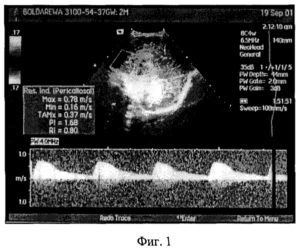

Наиболее точно поставить диагноз и установить степень нарушений позволяет допплерография. Этот метод фиксирует даже небольшие отклонения от нормы и полностью безопасен для беременной женщины и ее дитя.

Результаты допплерографии позволяют специалистам прогнозировать дальнейшее течение вынашивания плода, выбрать необходимую терапевтическую тактику.

На экране аппарата можно увидеть графическое цветное изображение кровотоков.

Допплерометрия

Такое необычное название имеет диагностическая процедура, выявляющая любые патологии кровотока в артериях и венах.

В результате на специализированной аппаратуре строится допплерограмма, на которой отображается разница частот между посланным и отраженным сигналом.

Исследование проводится в стандартном режиме либо с цветным картированием, то есть движение крови по артериям отображается в цвете. Последний вариант позволяет быстро и точно обнаружить даже легкое нарушение маточно-плацентарного кровотока.

Наиболее полноценную картину кровообращения между маткой и плодом получают при допплерографическом исследовании, которое проводится всем женщинам трижды за срок беременности.

Методика позволяет:

- измерить кровоток по скорости движения форменных элементов;

- определить его направление в артериях и венах;

- зафиксировать изменения до клинических проявлений.

Эффект основан на свойствах отражения ультразвуковой волны, совершенно безопасен для ребенка и матери

Все изменения регистрируются на мониторе, замеряются специальными датчиками, могут фотографироваться в необходимом формате.